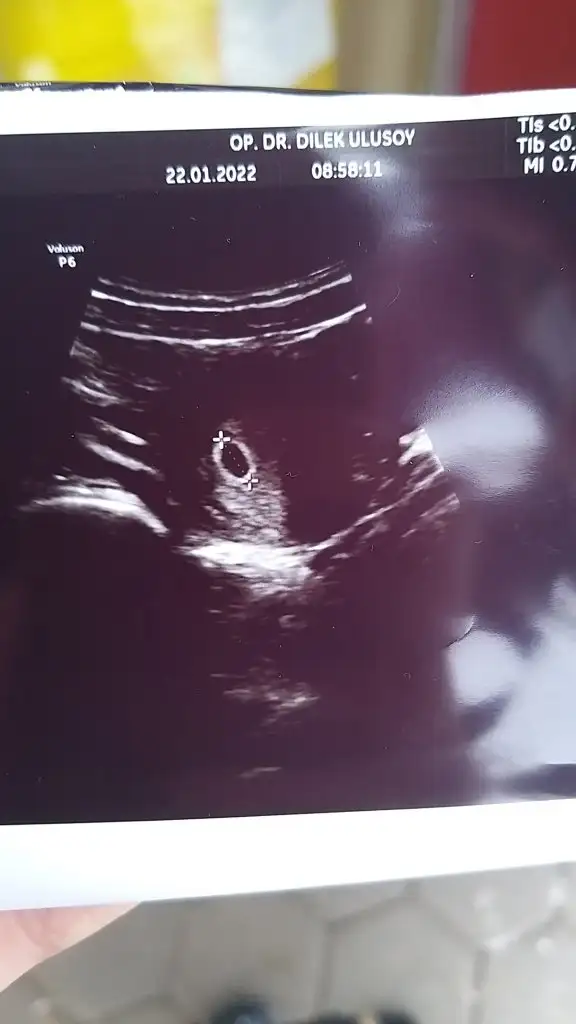

Cok sevindim canım var mı ultrason fotosuKesemizi gördük çok şükür teyzeleri5+2 mişiz haftaya kalp için çağırdı

Var teyzesi bakCok sevindim canım var mı ultrason fotosu

Oyy maşallah subhanallahVar teyzesi bak

Gözüün aydınnVar teyzesi bak